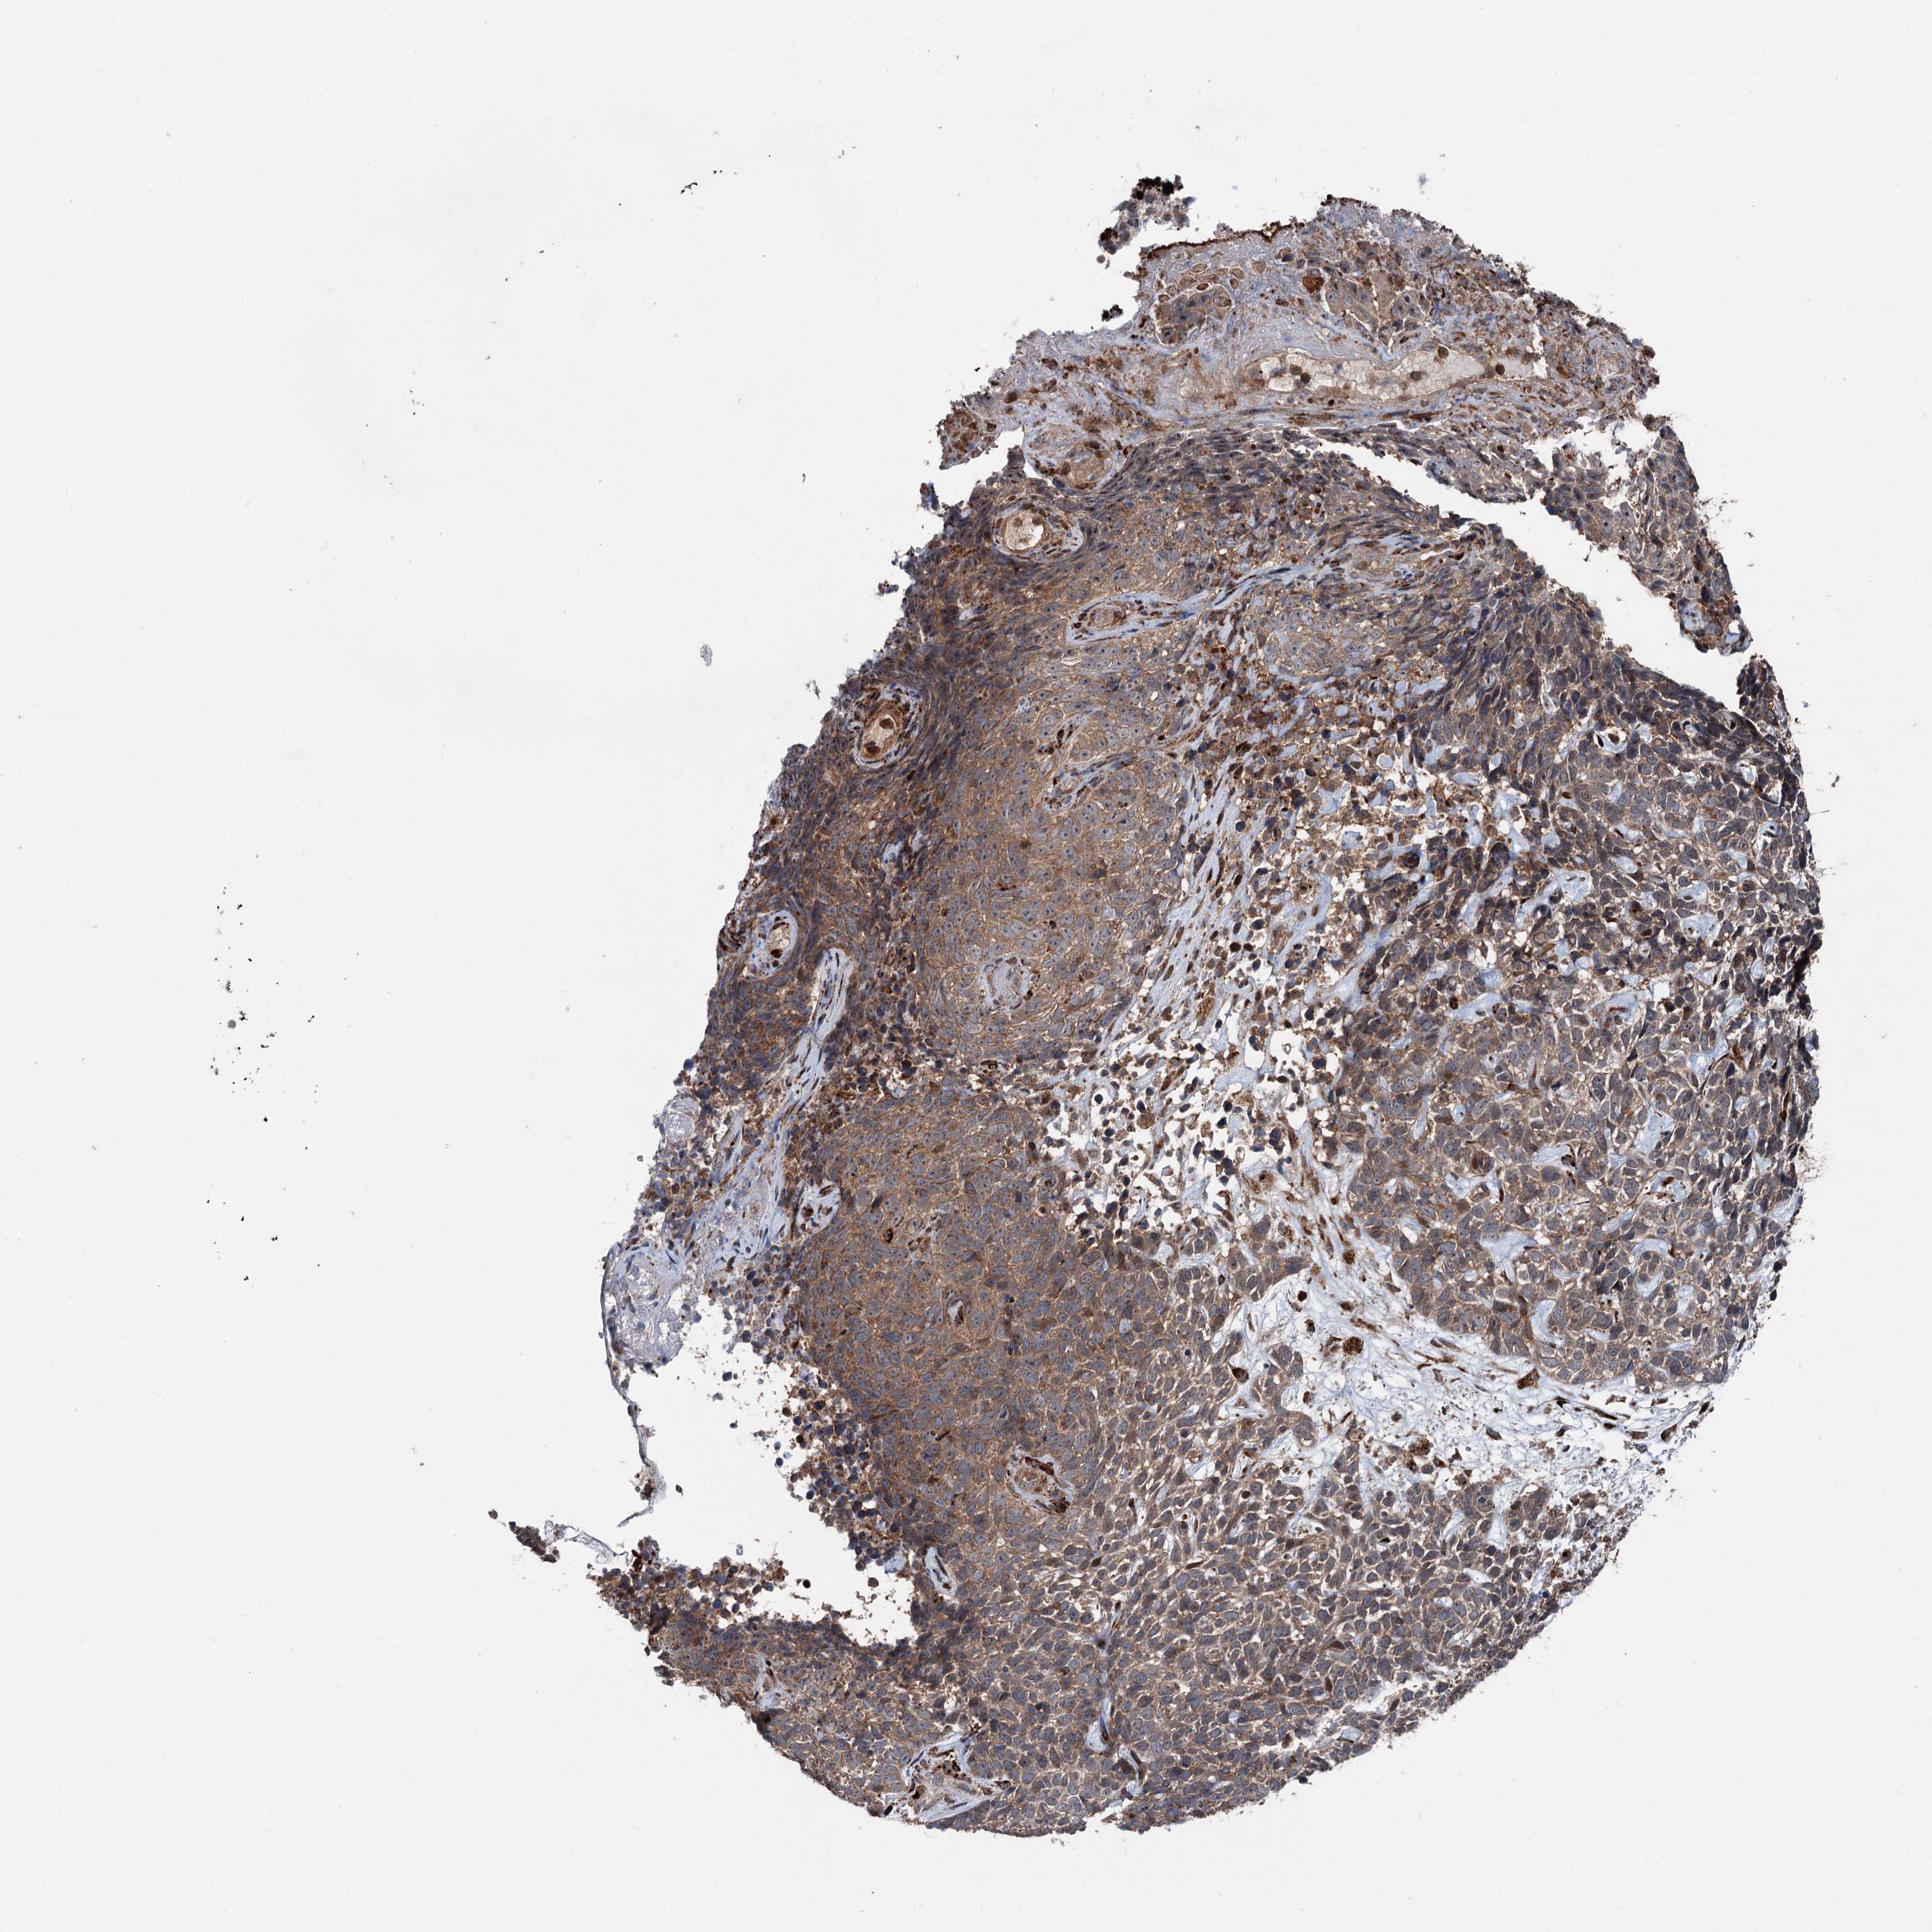

SKIN CANCER - Protein expressioni

A mouse-over function shows sample information and annotation data. Click on an image to view it in a full screen mode. Samples can be filtered based on level of antibody staining by selecting one or several of the following categories: high, medium, low and not detected. The assay and annotation is described here.

Antibody stainingi

Antibody staining in the annotated cell types in the current human tissue is reported as not detected, low, medium, or high, based on conventional immunohistochemistry profiling in selected tissues. This score is based on the combination of the staining intensity and fraction of stained cells.

Each image is clickable and will lead to virtual microscopy that enables deeper exploration of all samples and also displays staining intensity scores, fraction scores and subcellular localization as well as patient and tissue information for each sample.

Antibody HPA038540

Staining

High

Intensity

Strong

Quantity

>75%

Location

Nuclear

Basal cell carcinoma

Squamous cell carcinoma, NOS

Squamous cell carcinoma, metastatic, NOS